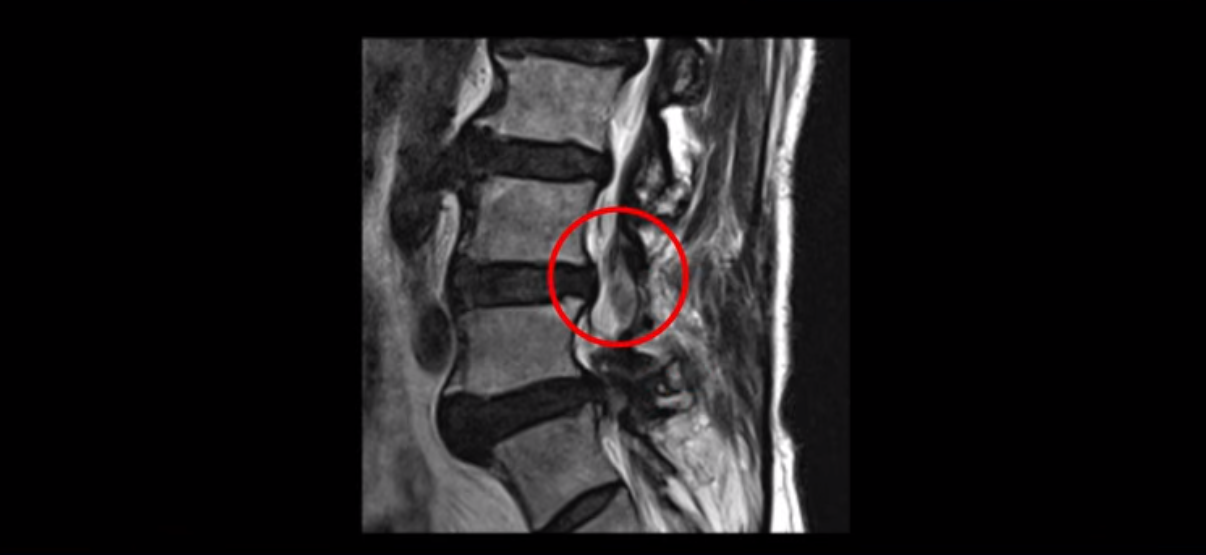

이 환자분은 협착증 수술을 두 번 받은 뒤에 또 다시 다리 방사통이 심해지고 발목 마비 증상(풋드랍)이 생겨서 이번에는 유합술을 권유받은 환자분입니다. 먼저 MRI를 보고 설명해 드린 후 이런 환자분의 방사통과 발목의 마비와 힘 빠짐이 어떻게 수술 없이도 좋아질 수 있는지 그리고 치료는 어떻게 하는지 자세히 설명드리겠습니다.

이분은 허리 다섯 마디 중 4번 5번, 5번 1번에 감압술로 눌린 신경을 풀어주는 수술을 받았습니다.

후관절을 떼어낸 흔적이 보입니다.

하지만 중심성 협착은 여전히 심한 상태입니다.

이분은 오른쪽, 왼쪽 다리에 모두 방사통이 심하고 왼쪽 다리에 마비 증상, 즉 풋드랍(족하수) 증상이 있습니다. 왼쪽 신경 가지가 빠져나가는 추간공을 보면 두 마디가 좁아져 있습니다.

이런 신경 구멍이 좁아져 있는 걸 협착이라고 합니다.

이미 앞선 두 번의 수술로 뼈와 인대 등을 일부 제거해서 안정성이 떨어진 상태에서 추가로 수술하려니까 척추가 너무 불안정해져 무너질 게 걱정되니까 이번에는 나사 박는 유합술을 권유 받은 겁니다. 이런 환자분들의 방사통과 마비 증상이 어떻게 수술 없이 좋아질 수 있을까요? 치료는 어떻게 하는 걸까요?